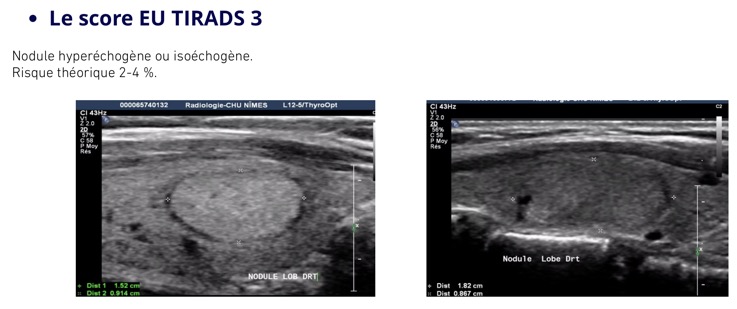

Se méfier des formations hypoéchogènes